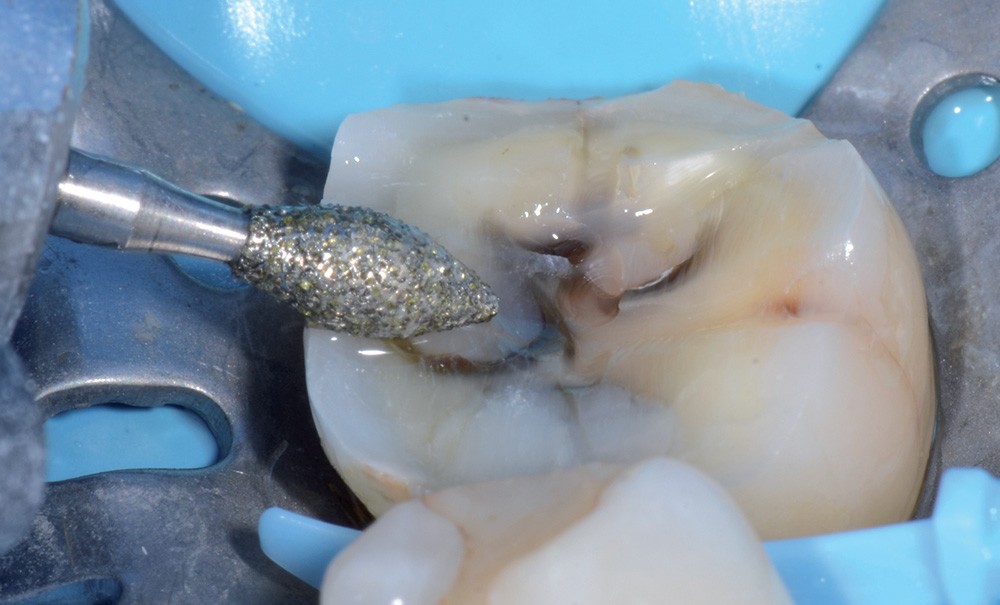

1 et 2. Un patient se présente à la consultation en raison d’une 36 douloureuse à la pression. La présence d’un inlay composite occluso-mésial ancien, infiltré, et des joints défectueux est constatée. L’analyse biomécanique révèle des fêlures, surtout au niveau de la crête marginale distale. Il faut de plus noter l’absence de la 37. Il est donc décidé de déposer la restauration et de réaliser un overlay en vitrocéramique de type e.max (Ivoclar Vivadent).

La fracture de la restauration (d’autant plus si le contexte occlusal est défavorable) ou le vieillissement prématuré du joint sont souvent dus à un non-respect des règles de préparation en fonction du matériau utilisé. Il est donc nécessaire de contrôler efficacement la profondeur de pénétration de la fraise dans la dent pour laisser la place minimale requise au matériau de restauration et préserver au maximum les tissus dentaires. Il convient de plus de maximiser la préservation de l’émail périphérique, garant de…